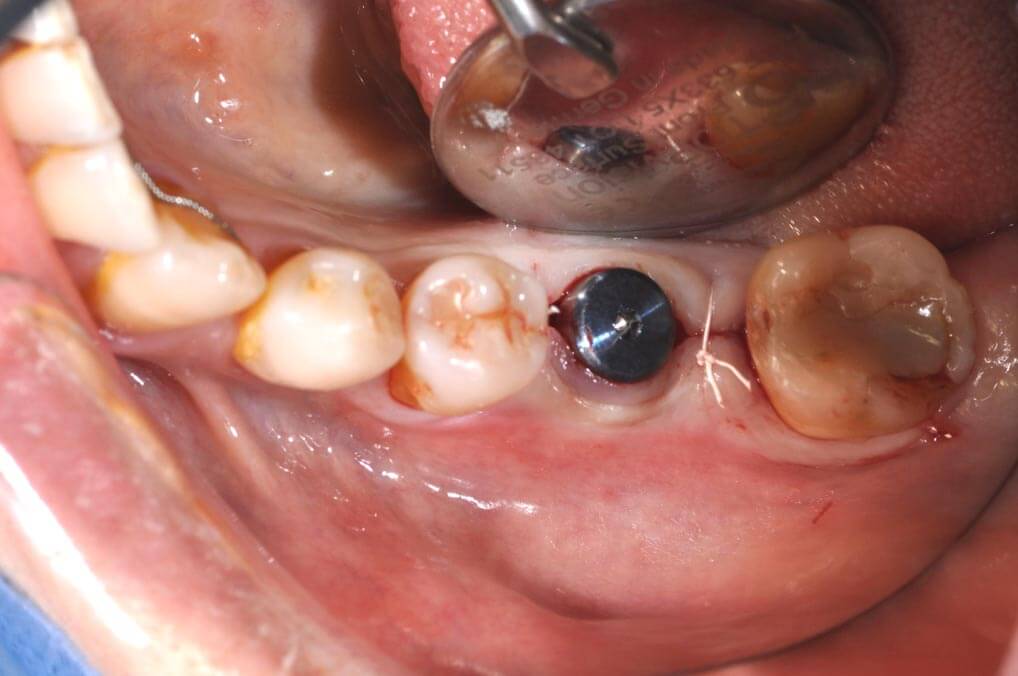

植牙過程一般分為兩個階段:第一階段先將植體放置於骨內,讓植體與骨結合;第二階段接出柱心並裝上假牙。整個療程約需3至6個月。

手術導引板 Surgical Guide 的使用

依照電腦的規劃結果,可製做出需要的手術導引版和相關的植牙零件,使得手術結果與電腦模擬達到零誤差。